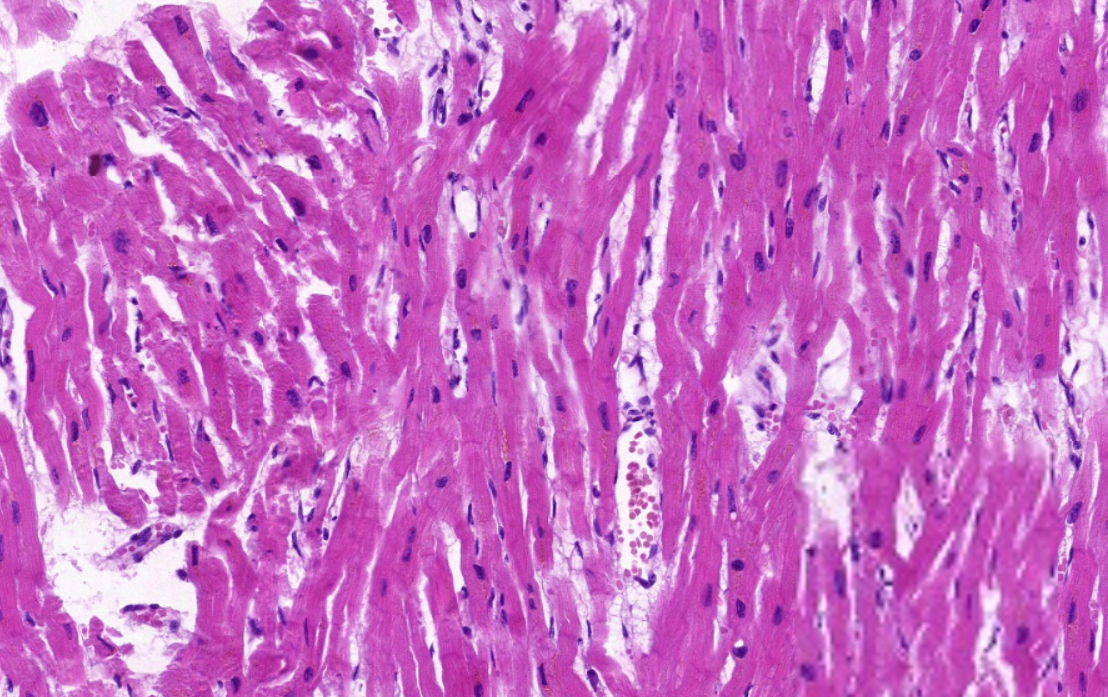

低倍镜结合高倍镜观察心壁分三层,由内向外观察:1. 心内膜:(1)内皮:较薄,表面为扁圆形的内皮细胞核。(2)内皮下层:其薄层结缔组织中含有少量平滑肌纤维。(3)心内膜下层:紧靠心肌膜为结缔组织,内含浦肯野纤维,其直径较一般心肌纤维粗,染色较浅,肌浆丰富,肌原纤维少,横纹不太明显。2. 心肌膜:最厚,占心壁的绝大部分,主要由心肌纤维组成,其间有结缔组织及丰富血管。3. 心外膜:为薄层结缔组织,富含毛细血管、神经及脂肪组织。其外表面被覆一层间皮。

4.心肌纤维